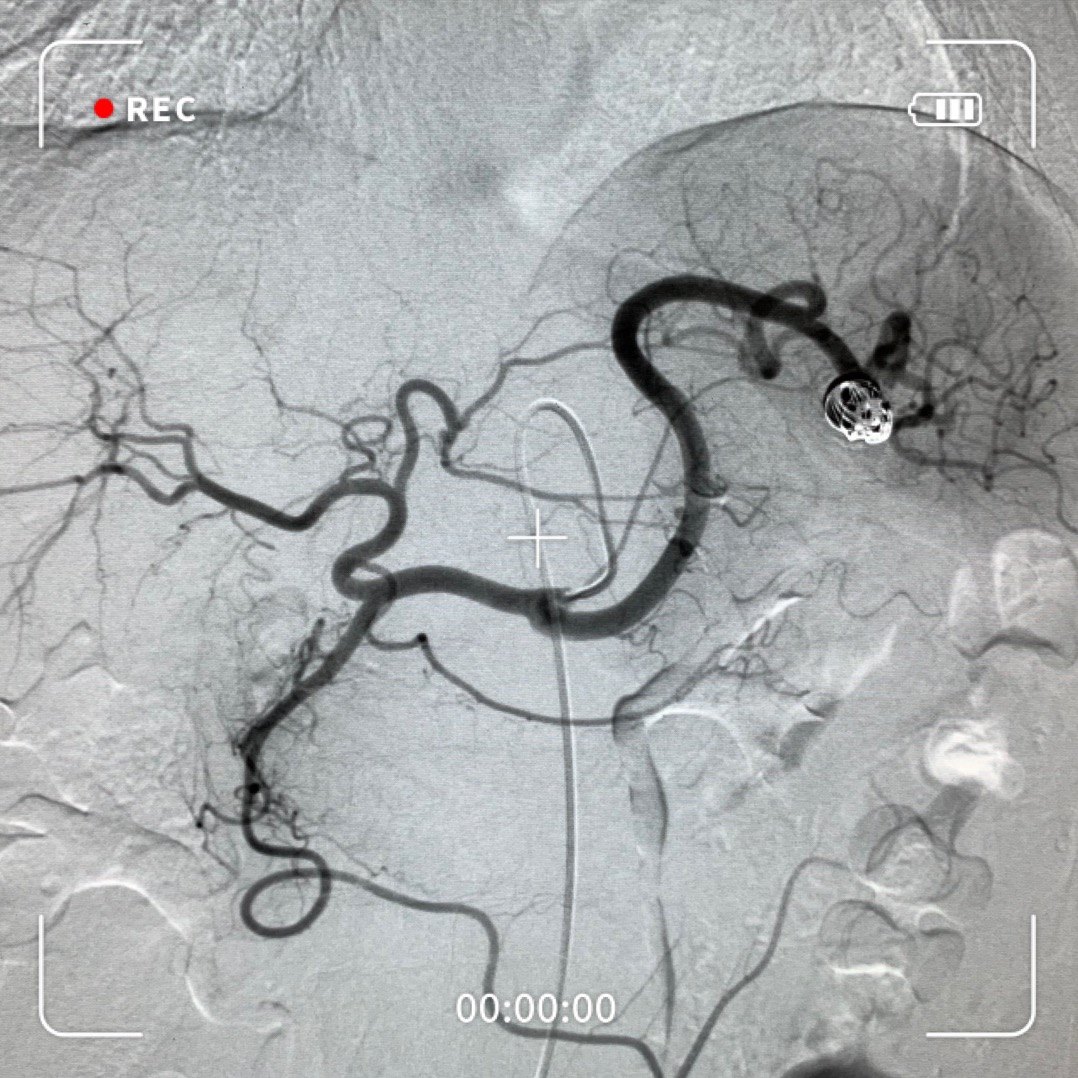

学影像之脾动脉介入

脾动脉瘤介入治疗一例